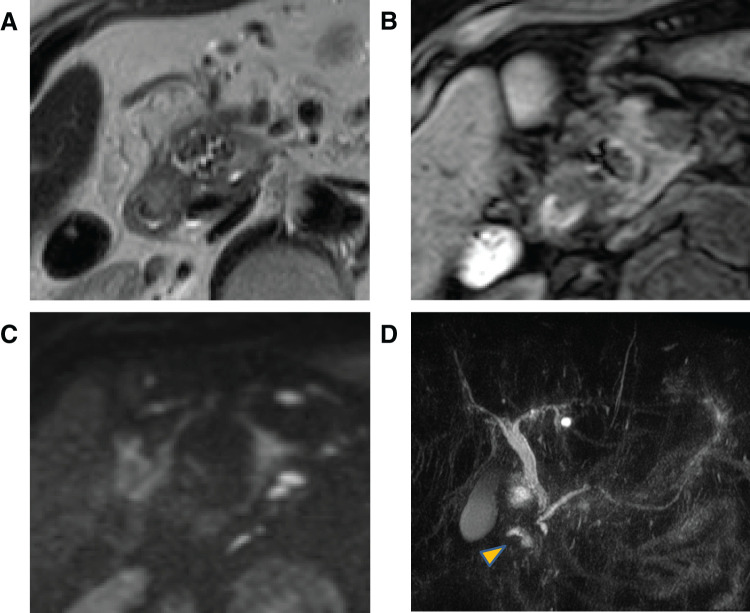

Case presentation: A 64-year-old man presented with groove pancreatitis attributable to heavy alcohol consumption and a hypovascular mass in the groove area with duodenal bleeding. The lesion, which was initially considered a pancreatic groove tumor with groove pancreatitis, was treated with subtotal stomach-preserving pancreaticoduodenectomy. However, a post-surgical pathological analysis revealed that it was a pancreatic pseudocyst in the groove area containing bilirubin calcium stones and pancreatic stones.

Conclusions: Cases comprising fistula formation in the common bile duct are rare. A pancreatic pseudocyst that formed a fistula with the common bile duct was suspected in the present case. This case was unique because the pseudocyst was filled with microbiliary stones. This report highlights the difficulty in differentiating a pseudocyst filled with bilirubin calcium stones from a neoplastic lesion and underscores the importance of the accurate diagnosis and management of this rare pathology.